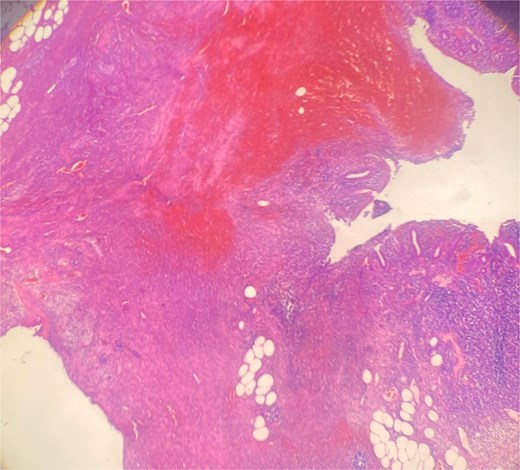

Histopathology confirmed gangrenous appendicitis with perforation (Figs 1 and 2). The postoperative course was uneventful; peristalsis returned on Day 2, with meticulous follow-up of laboratory parameters, gradual mobilization and restauration of bowel function from Days 3–7, and the patient was discharged on Day 7 in good condition.

Hematoxylin Eosin (HE) stain 100× transmural acute inflammation with peritonitis.